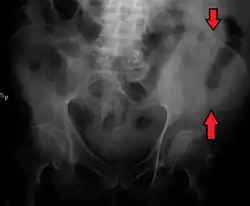

The top of the iliac crests also marks the level of the fourth lumbar vertebral body (L4), above or below which lumbar puncture may be performed. Furthermore, said level is often referred to as the "intercristal line".

Iliac crest labeled at center right

Iliac crest